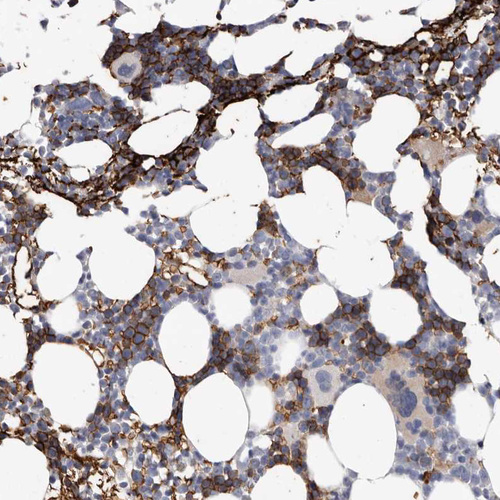

Immunohistochemical staining of human bone marrow shows moderate membranous positivity in hematopoietic cells.